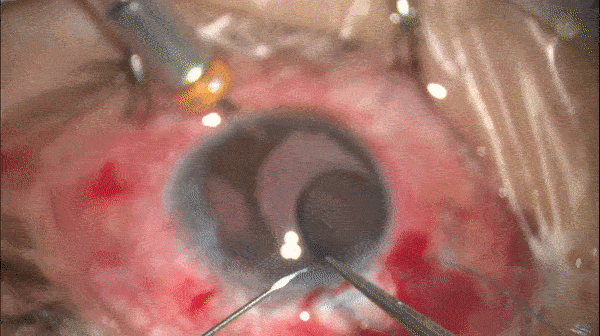

Step 14

虹膜塑形

牵拉虹膜使粘连的虹膜松解,瞳孔成形。

开睑器怎么用术说睛彩 | 金海鹰教授:使用8-0缝线的无巩膜瓣人工晶体固定手术_https://www.jmylbn.com_新闻资讯_第24张